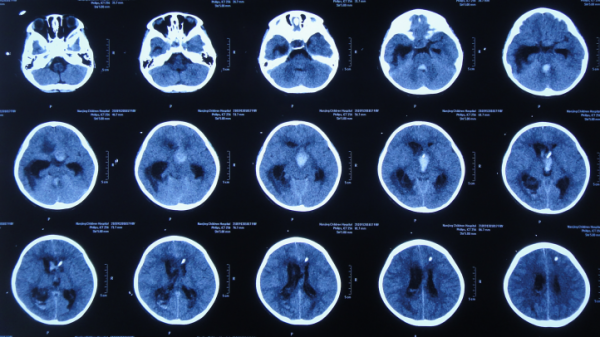

在第4家醫院治療26天期間內,三次複查頭部CT(圖-29、圖-30、圖-31)均示腦積水,右側顳角明顯擴。

圖-29:2020年4月23日頭部CT

圖-30:2020年5月7日頭部CT

圖-31:2020年5月18日頭部CT

看著患兒病情無好轉,家屬心急如焚,在網上找到李小勇腦脊液科經確認後於2020年5月19日(在第4家醫院治療26天)從安徽省蕪湖市轉入北京北亞骨科醫院的李小勇腦脊液科。